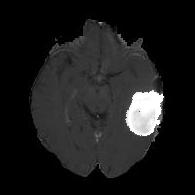

We argue that the sub-optimal paradigm of processing different abstractions within a single CNN pipeline can be remedied through the effective processing of information in a structured manner. Consequently, we devise strategies for disentangling the edge and texture information within a single training pipeline. Figure 2 illustrates how our proposed module, dubbed EG-CNN, can be paired with any existing CNN encoder-decoder to improve segmentation quality near intensity edges. We have applied our EG-CNN to the tasks of brain and liver tumor segmentation in medical images (Figure 3).

(1) Brain MR (2) Liver MR (3) Liver CT (4) Lung CT